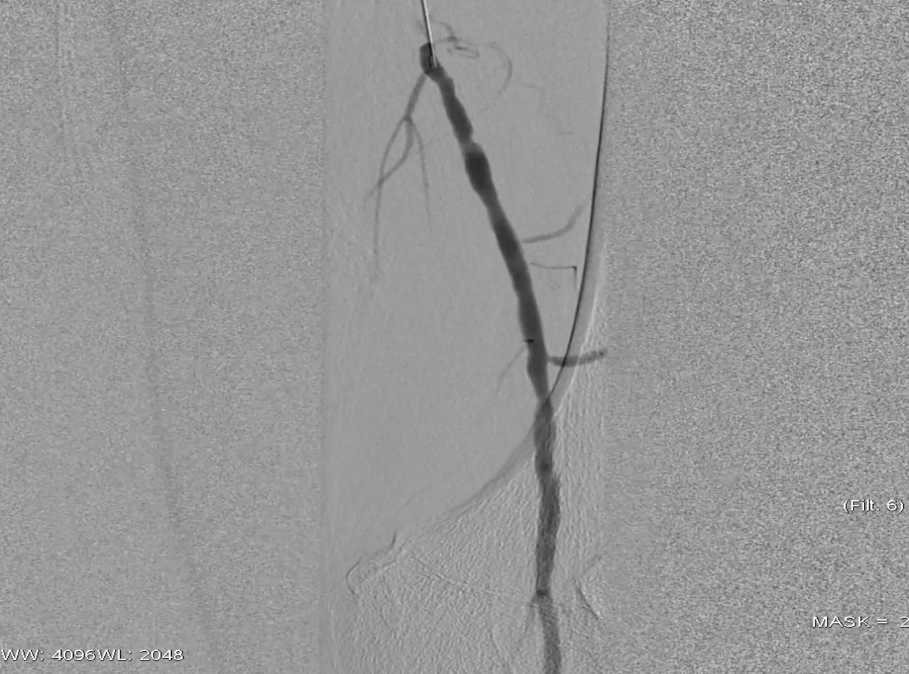

栓塞处理:造影发现管腔获得尚可,但是流速明显较慢,考虑保护伞上方管腔闭塞(考虑斑块/血栓脱落),用6F导管反复抽吸后收回保护伞。

夹层发现及处理:

更换V18导丝后造影显示,胫后动脉血流通畅,胫前动脉疑似仍有小的血栓脱落,导致栓塞。

股浅动脉全程管腔获得尚可,但中段有明显的夹层形成,

先用5mm长球囊充分预扩张;再次造影显示,股浅动脉近中段管腔获得良好,中远段仍有大量的夹层

采用药物涂层球囊(DCB)对股浅动脉病变段全程覆盖:近端用5-250新型药涂球囊,远端用5-150 impact 药涂球囊;

造影显示中段仍有局限性夹层,为保证远期通畅率,植入补救性支架并以5mm球囊后扩张